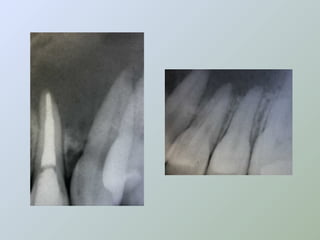

A técnica radiográfica deve ser muito bem

realizada, para a visualização adequada do

ápice radicular, e a determinação da

extensão de lesões e relações com

estruturas anatômicas adjacentes.

BRAMANTE; BERBERT, 1991 e 2000;

ORSTAVIC, 1991 e SAILER; PAJAROLA,

2000.